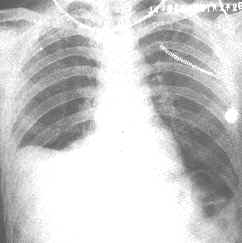

類肺炎性胸腔積液其他輔助檢查:肺的物理檢查結合胸部的X線徵象對中等量以上的積液確定較易,而少量胸腔積液則要通過細緻的檢查才能確定。前後位或側位胸片肋膈角模糊或變鈍,或膈肌模糊者提示有胸腔積液,可改變體位透視或側臥位胸片確定,此時液體散開,肋膈角或膈肌變清晰。CT對胸腔積液診斷效率更高,還可鑑別肺和胸膜病變,了解肺實質病變的位置和特徵,有助於鑑別診斷和指導治療。此外,超音波檢查也可確定有無胸腔積液存在和穿刺定位。